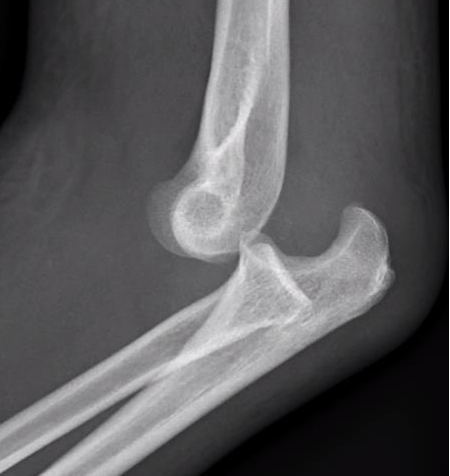

Posterolateral rotatory subluxation / instability

Incomplete posterolateral dislocation

Coranoid perches on trochlea